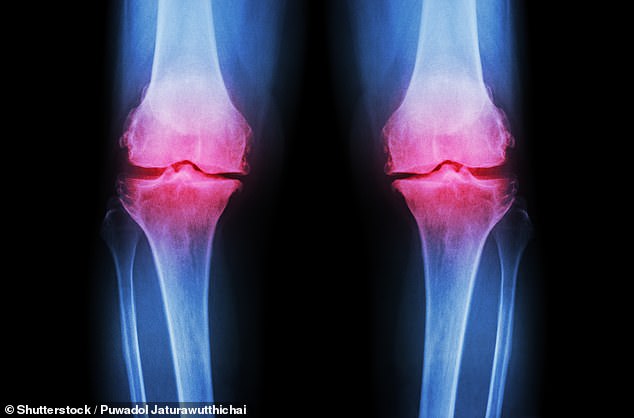

Osteoarthritis, the most prevalent form of arthritis in the UK, affects approximately 10 million people and is characterized by the progressive degradation of cartilage that cushions joints. As this protective tissue wears away, joints become painful, stiff, and increasingly difficult to move. Current treatments often rely on pain medications, which carry risks of side effects, or physiotherapy, which many patients struggle to maintain consistently. This study presents an alternative: a simple dietary intervention that could complement existing therapies and reduce reliance on pharmaceuticals.

Results revealed that both inulin and physiotherapy independently reduced knee pain over six weeks. However, inulin demonstrated additional benefits, including improved grip strength and reduced pain sensitivity—a critical factor for individuals with osteoarthritis, who often experience heightened sensitivity to even mild pressure or movement. The study also measured changes in GLP-1, a gut-derived hormone linked to muscle function and pain regulation, which increased significantly in the inulin group compared to controls.